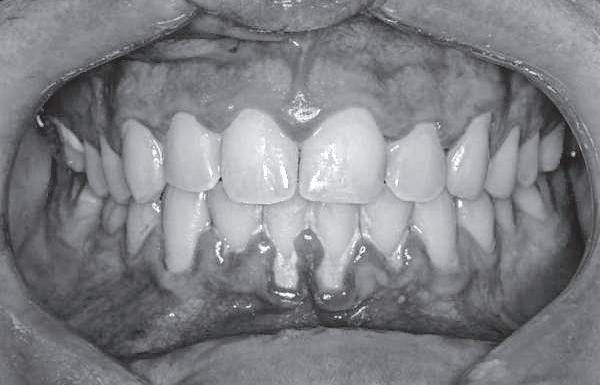

periodoncia

A la pregunta qué patologías más comunes tiene la gente que consultaba al odontólogo, el doctor Palavecino mencionó que, como era el único periodoncista y el primer odontólogo que hacía cirugía plástica gingival en junín y zona, tenía muchas derivaciones desde los mismos colegas.

“El fuerte mío es la periodoncia. Cuando empecé a trabajar como odontólogo vi que era fundamental este tema, en una oportunidad asistí a un congreso y escuché a un

periodoncista en Pergamino que lo había presentado el Colegio de Odontólogos y decidí que eso era lo que quería hacer. Me contacté con ellos, tomé cursos con Raúl y Maxi-

miliano Chacón, periodoncistas que dan los cursos en el Círculo Odontológico de Rosario”, dijo.

“La periodoncia tiene que ver con todo lo relacionado

con la inserción y protección del diente y la raíz, donde está insertado y anclado el diente y protegido por la encía- explicó-. Por eso se relaciona con muchas otras cosas, con todas las especialidades de la odontología porque es la base para tener los tejidos peridentarios, es decir que rodean al diente, en estado de salud. La encía y el hueso tienen que estar en estado de salud para rehabilitar un diente y se empieza por ahí. No se puede tener una patología en la encía y rehabilitar. Si la patología está sangrante, inflamada,

complica para hacer una buena rehabilitación”.

El doctor Palavecino explicó también como podía influir una enfermedad en las encías en el resto del cuerpo. “Una infección en la encía y/o hueso, gingivitis y/o periodontitis cuando afecta al hueso además de la gíngiva, se relaciona con un montón de patologías, incluso a nivel sistémico por ejemplo el Alzheimer, la diabetes, la predisposición a infarto de miocardio, a un ACV, en las embarazadas puede ser el aborto espontáneo, bajo peso del neonato, y en los deportistas de alto rendimiento, desgarro, rotura de ligamentos”, detalló.

“Esto tiene relación con todos los órganos del organismo porque todas las bacterias y las toxinas, las sustancias químicas que se liberan en el proceso inflamatorio por la infección en las encías viajan a través del torrente sanguíneo y por eso afecta a todo el organismo y se expone a un montón de otras patologías”, explicó.

También dio un dato a tener en cuenta: La gingivitis- periodontitis, la enfermedad de las encías, afecta a más del 90 por ciento de la población mundial, según las estadísticas. Por su parte, dijo que las recomendaciones para evitar esta enfermedad eran la higiene bucal (con cepillo, hilo dental) y el control profesional para no tener placa bacteriana.<